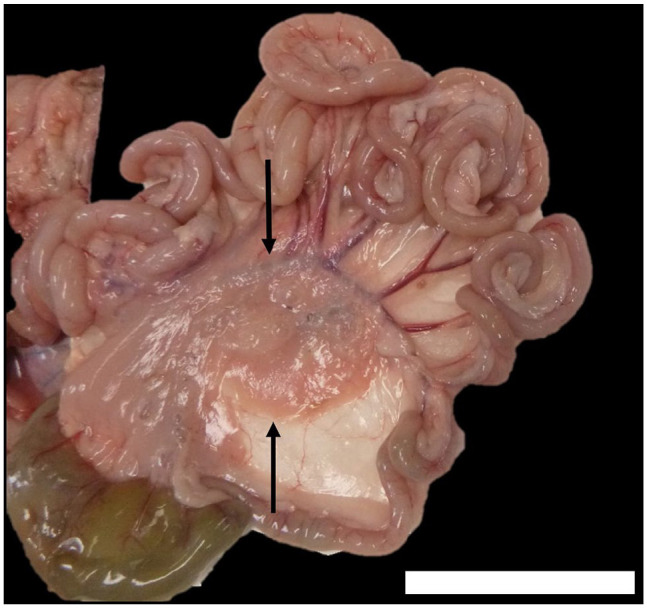

Case summary: An 8-year-old female spayed Russian Blue cat presented for acute progressive dyspnoea. The patient had pleural effusion and was diagnosed with chylothorax. A multiphase contrast-enhanced CT scan of thoracic and abdominal cavities was performed to facilitate diagnosis and surgical planning. Incidentally, a large lobulated, elongated, cystic and encapsulated peritoneal mass was found. Contrast pooled within the peritoneal mass during lymphography, suggesting lymphatic origin. The patient was eventually euthanased as a result of recurrence of chylothorax. Necropsy revealed multiple irregular, thin-walled pockets of chylous fluid pooling within the mesentery. Histopathology of the affected mesentery was compatible with a diagnosis of lymphatic malformation.

Relevance and novel information: To the authors' knowledge, this is the first case describing a feline presentation of mesenteric lymphatic malformation. This is also the first case reporting the presentation of chylothorax for a veterinary patient with mesenteric lymphatic malformation.